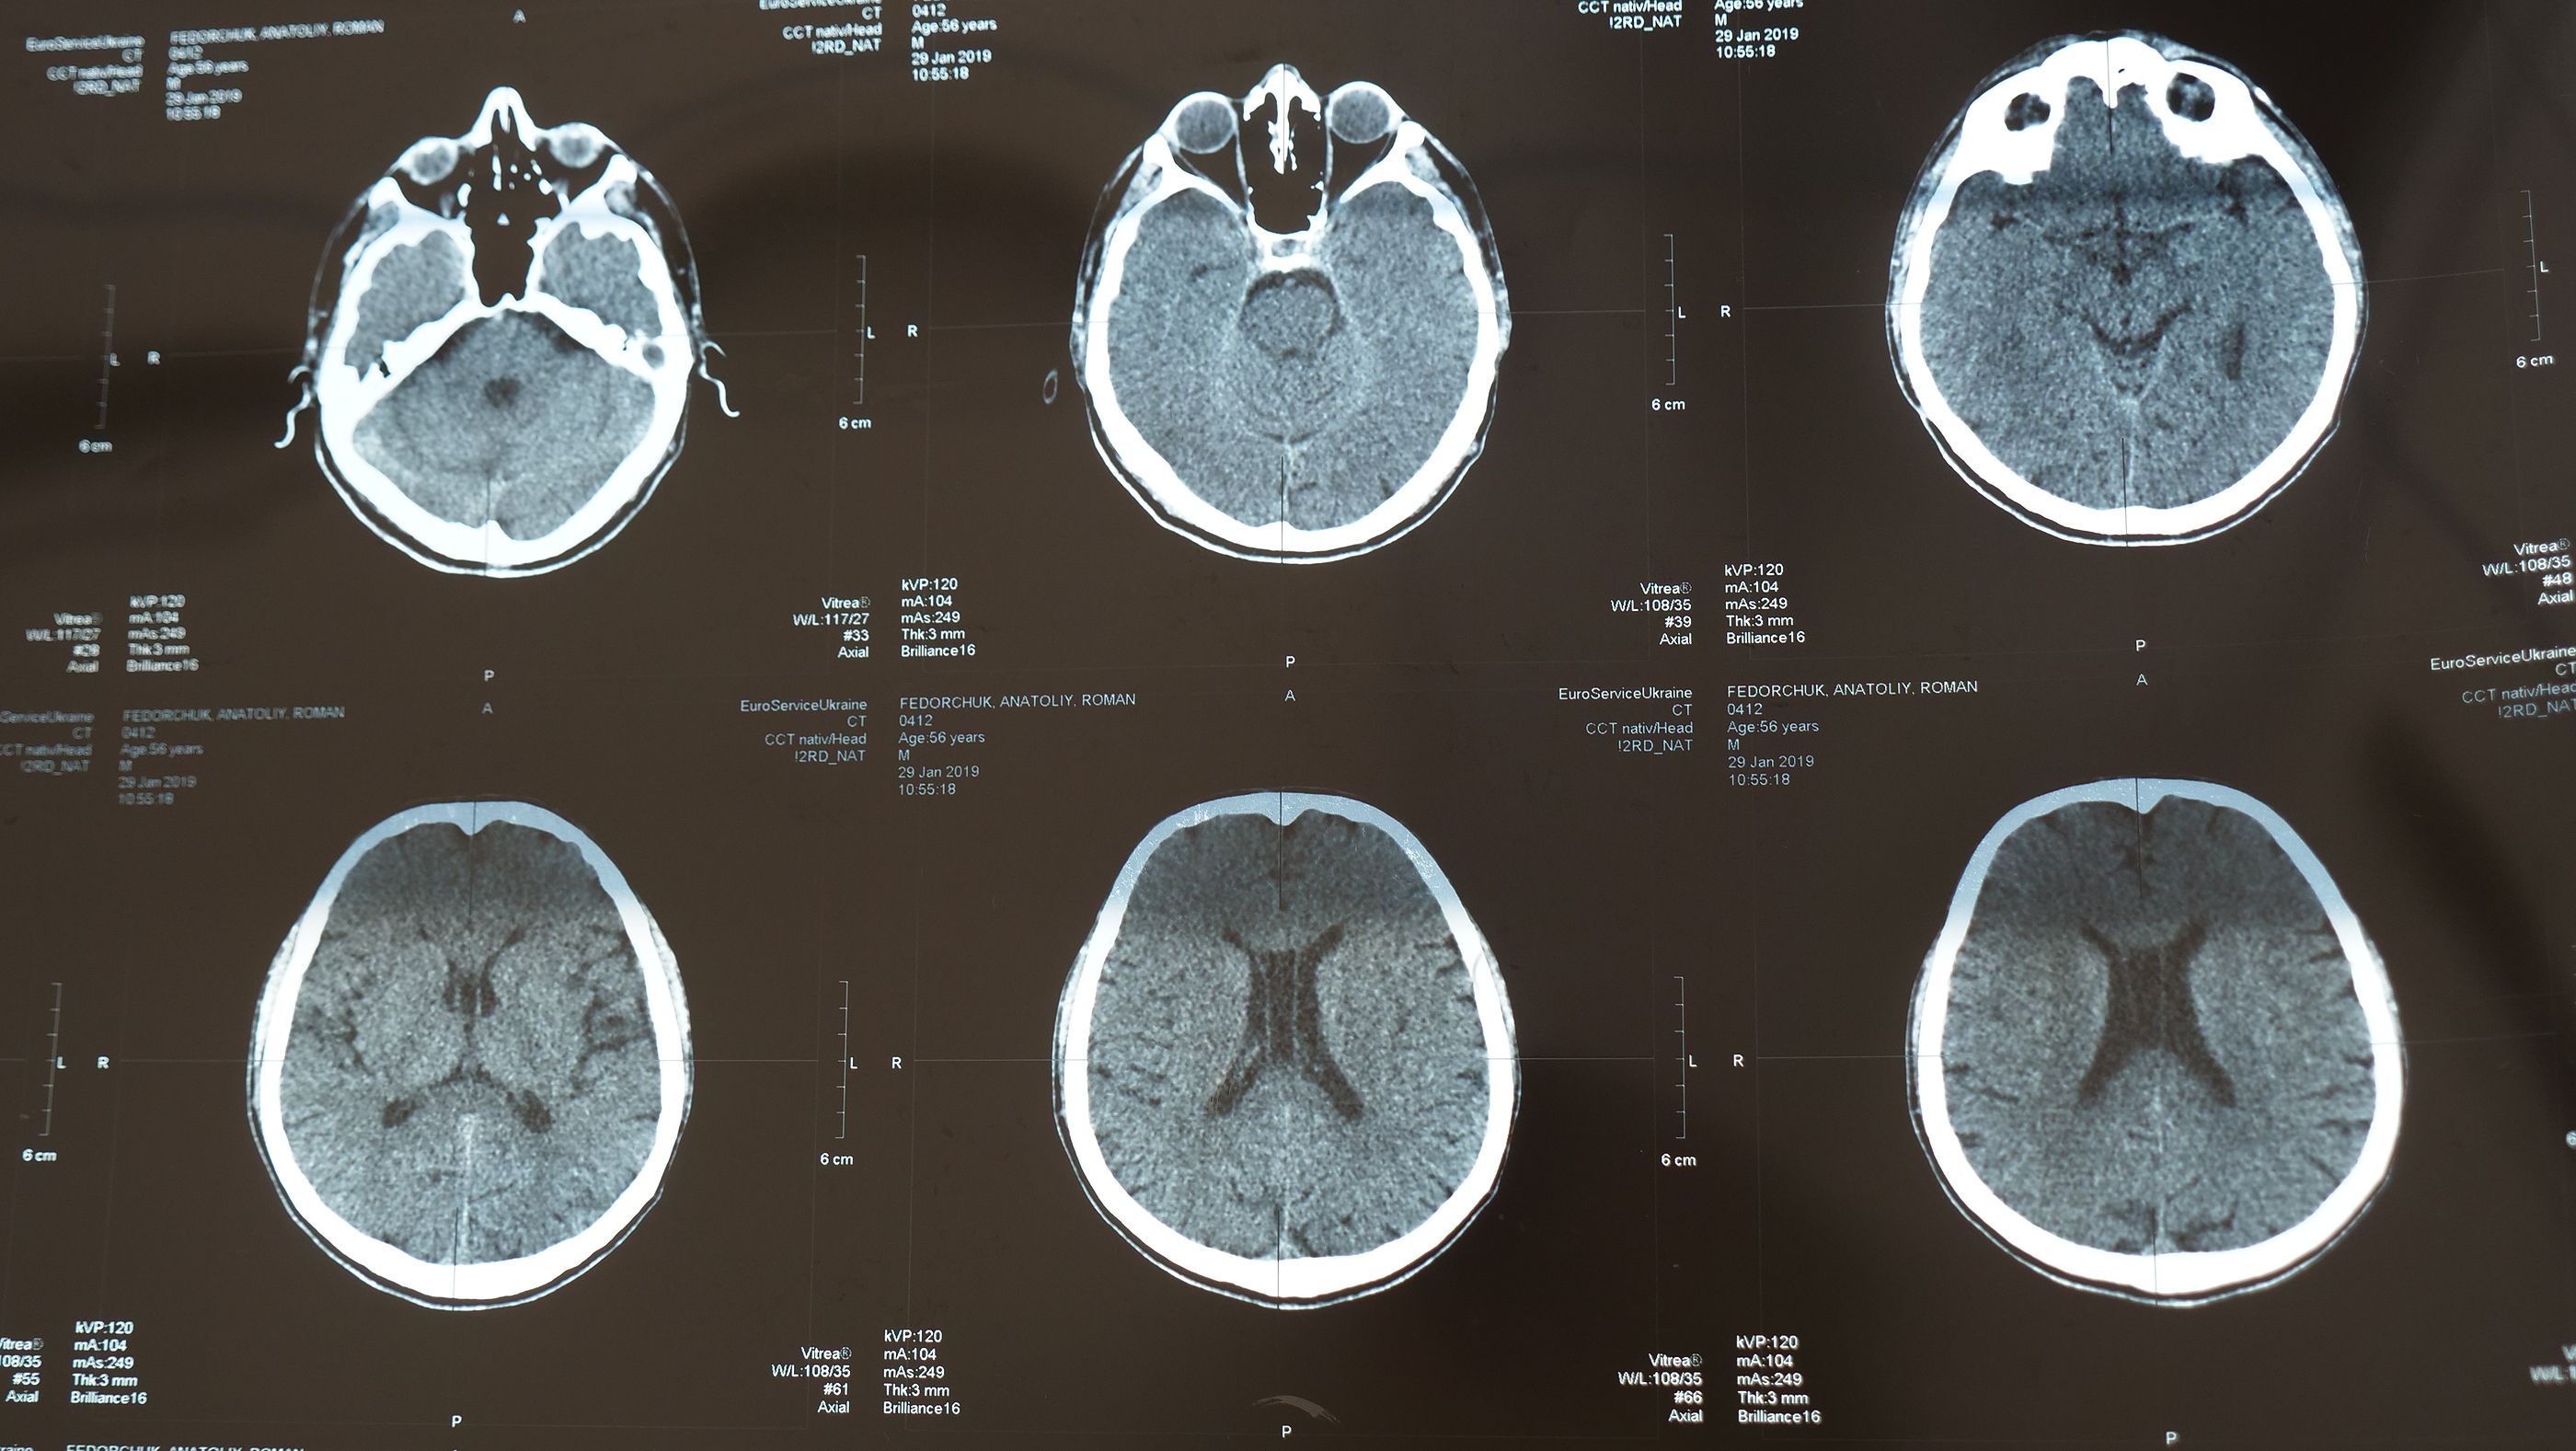

El tratamiento hizo desaparecer el tumor de su garganta y de la metástasis en sus pulmones se encargaron la quimioterapia y la cirugía. Pero su caso no es el único beneficiado por esta terapia, la extensión de vida media de los pacientes con cánceres cerebrales recidivantes o metástasis que la reciban es de 17,6 meses, apuntan los autores del estudio.

El tratamiento, que se está mostrando incluso más eficaz que la quimioterapia en enfermos con tumores en cabeza y cuello combina dos fármacos que logran reforzar el sistema inmunitario, el nivolumab y el ipilimumab.